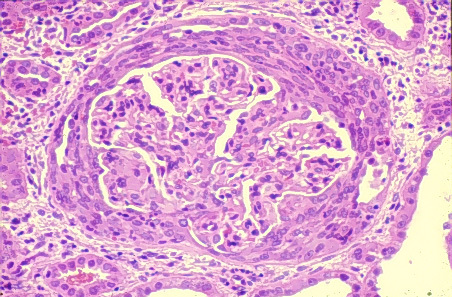

Renal presentation in goodpasture sydnrome